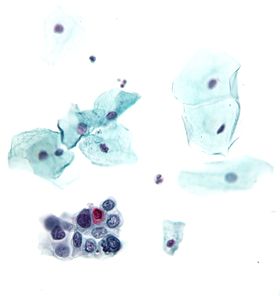

High-grade squamous intraepithelial lesion | |

- High-grade squamous intraepithelial lesion (HGSIL or HSIL)

Pap tests commonly look for epithelial abnormalities/ metaplasia/ dysplasia/ borderline changes, all of which may be indicative of CIN. Nuclei will stain dark blue, squamous cells will stain green and keratinised cells will stain pink/ orange. Koilocytes may be observed where there is some dyskaryosis (of epithelium). The nucleus in koilocytes is typically irregular, indicating possible cause for concern; requiring further confirmatory screens and tests.